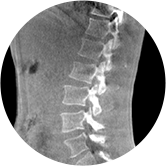

三维脊柱应用

精准诊断

手术方案规划

术后随访

• 脊柱评估

传统方法都是在二维平面,依靠棘突或椎弓根相对于椎体的偏移来评估脊柱侧凸。WR-3D可以更精准评估脊柱侧凸,制定手术方案,可以更直观地显示和量化椎体的平移和轴向旋转,术后评估更准确客观。